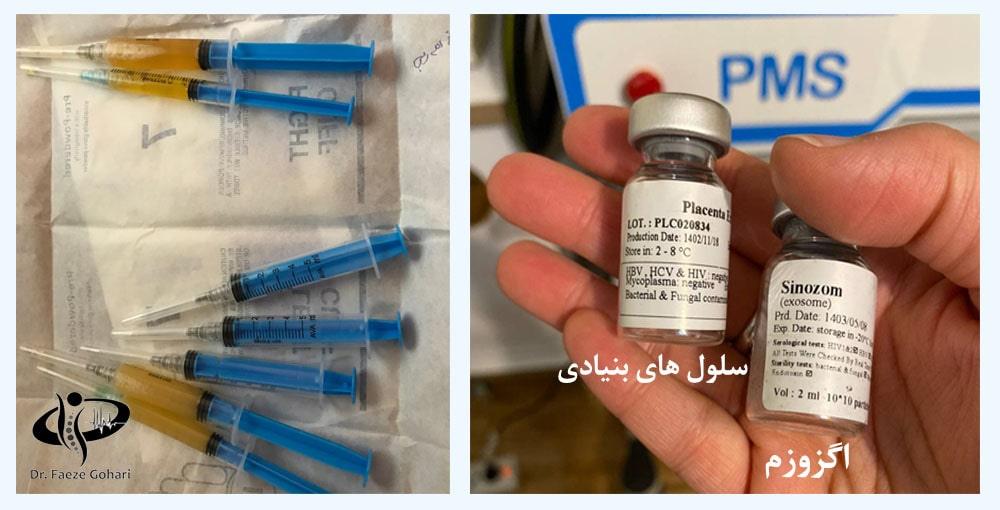

3. ترکیب پیآرپی، سلولهای بنیادی و اگزوزوم

سلولهای بنیادی (تهیهشده از بانک سلولی) همراه با پیآرپی استخراجشده از خون بیمار و اگزوزوم (که از بانک سلولی نیز تهیه شده) ترکیب میشوند و بهصورت یک کوکتل برای تزریق به زانو به طور آماده میشوند.

- تهیه سلولهای بنیادی و اگزوزمهای با کیفیت بالا از بانکهای سلولی معتبر برای کاهش احتمال پسزدگی

در کلینیک دکتر گوهری، سلولهای بنیادی تنها از بانکهای سلولی معتبر و دارای مجوز تهیه میشوند. تمامی فرآیندها تحت نظارت دقیق پزشک قرار دارد و هیچ گونه عوارض جانبی گزارش نشده است.